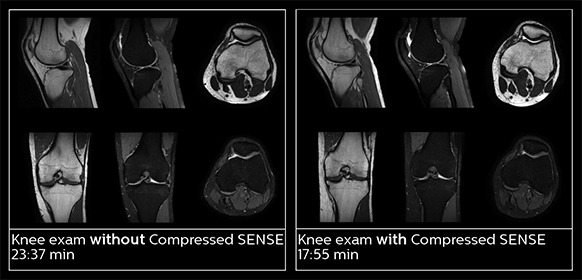

Utilizing MR in the emergency department means a prioritizing speed to enable a quick diagnosis. However, accelerating scans can compromise imaging quality and can result in blurry images. Through Compressed SENSE, an application that enhances productivity in imaging by increasing the data that is able to be pulled quickly from scans, including both 2D and 3D scans, all anatomical contrasts and all anatomies.